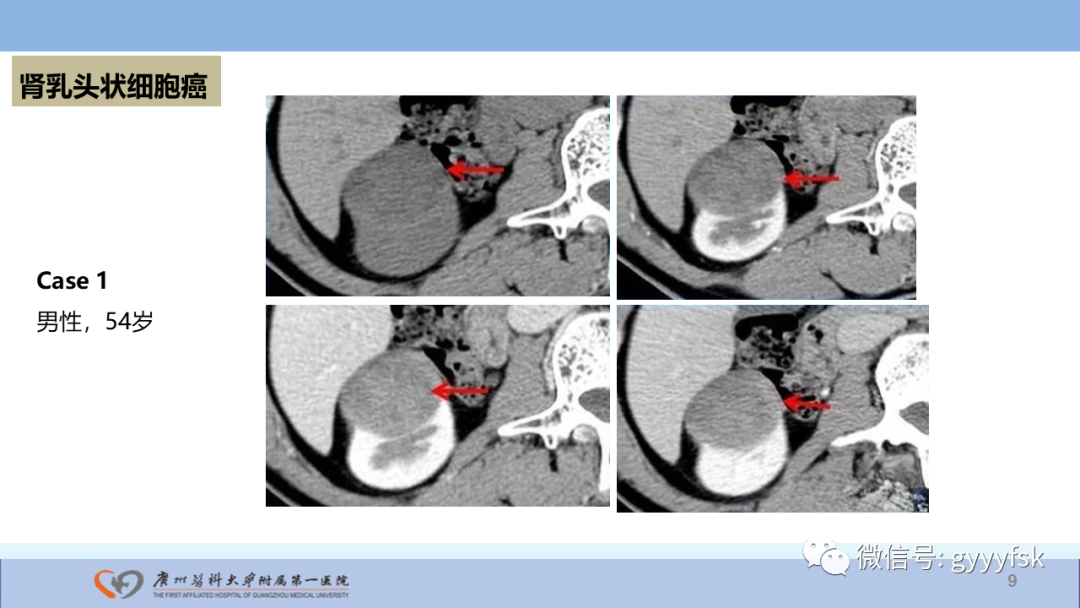

【PPT】肾癌相关影像诊断的文献汇报-9